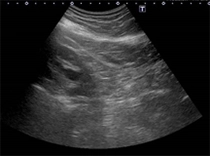

左腎エコー

左腎エコー左水腎症

左水腎症

神経因性膀胱が長期にわたり続いた結果、膀胱尿管逆流症を併発し両側水腎症(腎臓に尿がたまっている状態)を合併しています。この状態が長期間続くと腎機能の増悪に至ります。

写真の症例は、内科で過活動膀胱の薬を処方されている状態でした。

困ったことに、神経因性膀胱の患者さんは、尿意も鈍化しており残尿多量な状態に気づかない患者さんも多いです。